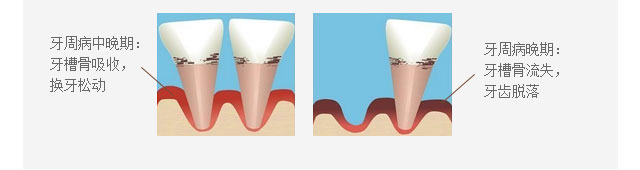

牙周病是什么——缺牙的元凶

牙周疾病我国发病率最高的口腔疾病,是引起成年人牙齿丧失的主要原因之一,是危害人类牙齿和全身健康的主要口腔疾病。常见的牙周病包括牙体硬组织疾病、牙髓病、牙根尖周病、牙周组织病和口腔黏膜病等等,如果治疗不及时,牙齿松动掉落是常见的表现,此外还会引发其他严重并发症。牙周病只能防治,无法根治!

牙周组织健康参考图